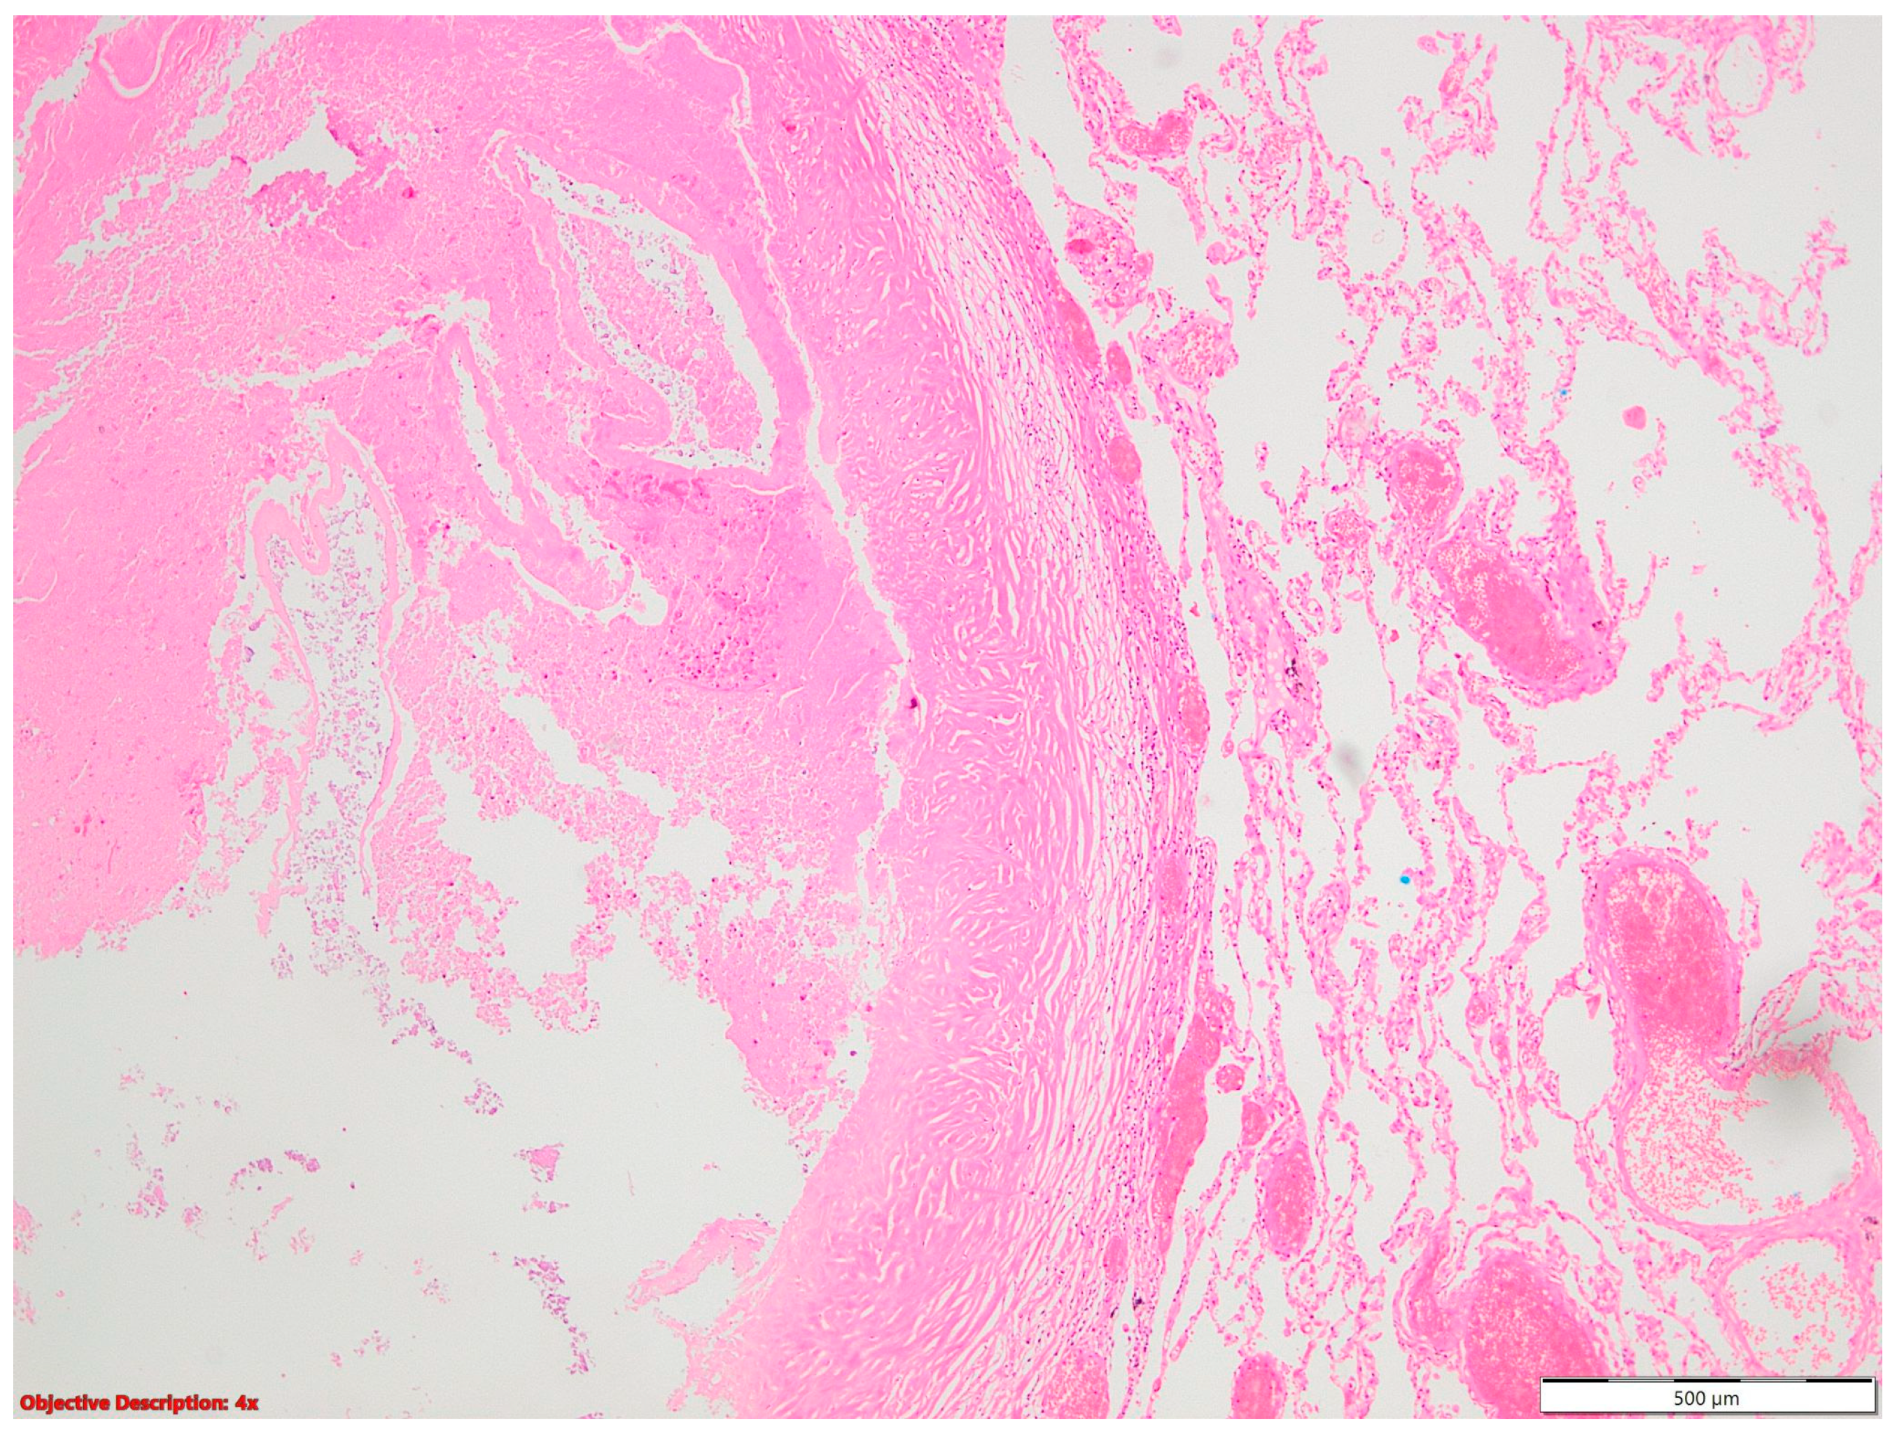

A histopathological examination of surgical resection specimens highlighted the presence of the following associations between NSCLC and other tumoral and nontumoral, and infectious and noninfectious pathological lesions, including nine cases of granulomatous inflammation, ten cases of fibronodular lesions, five cases of fibronecrotic nodules (Figure 1), two nodular calcifications, four instances of osseous/osteomedullary metaplasia, three cases of pneumoconiosis, two benign tumors, four lung infarctions, one instance of aspiration pneumonia, and one meningothelial-like nodule (Table 1).

Figure 1.

Fibronecrotic nodule (left side) in the lung parenchyma (right side); HE, 40×.

Figure 4.

Fibronodular lesion (left side) in the lung parenchyma (right side); HE, 40×.